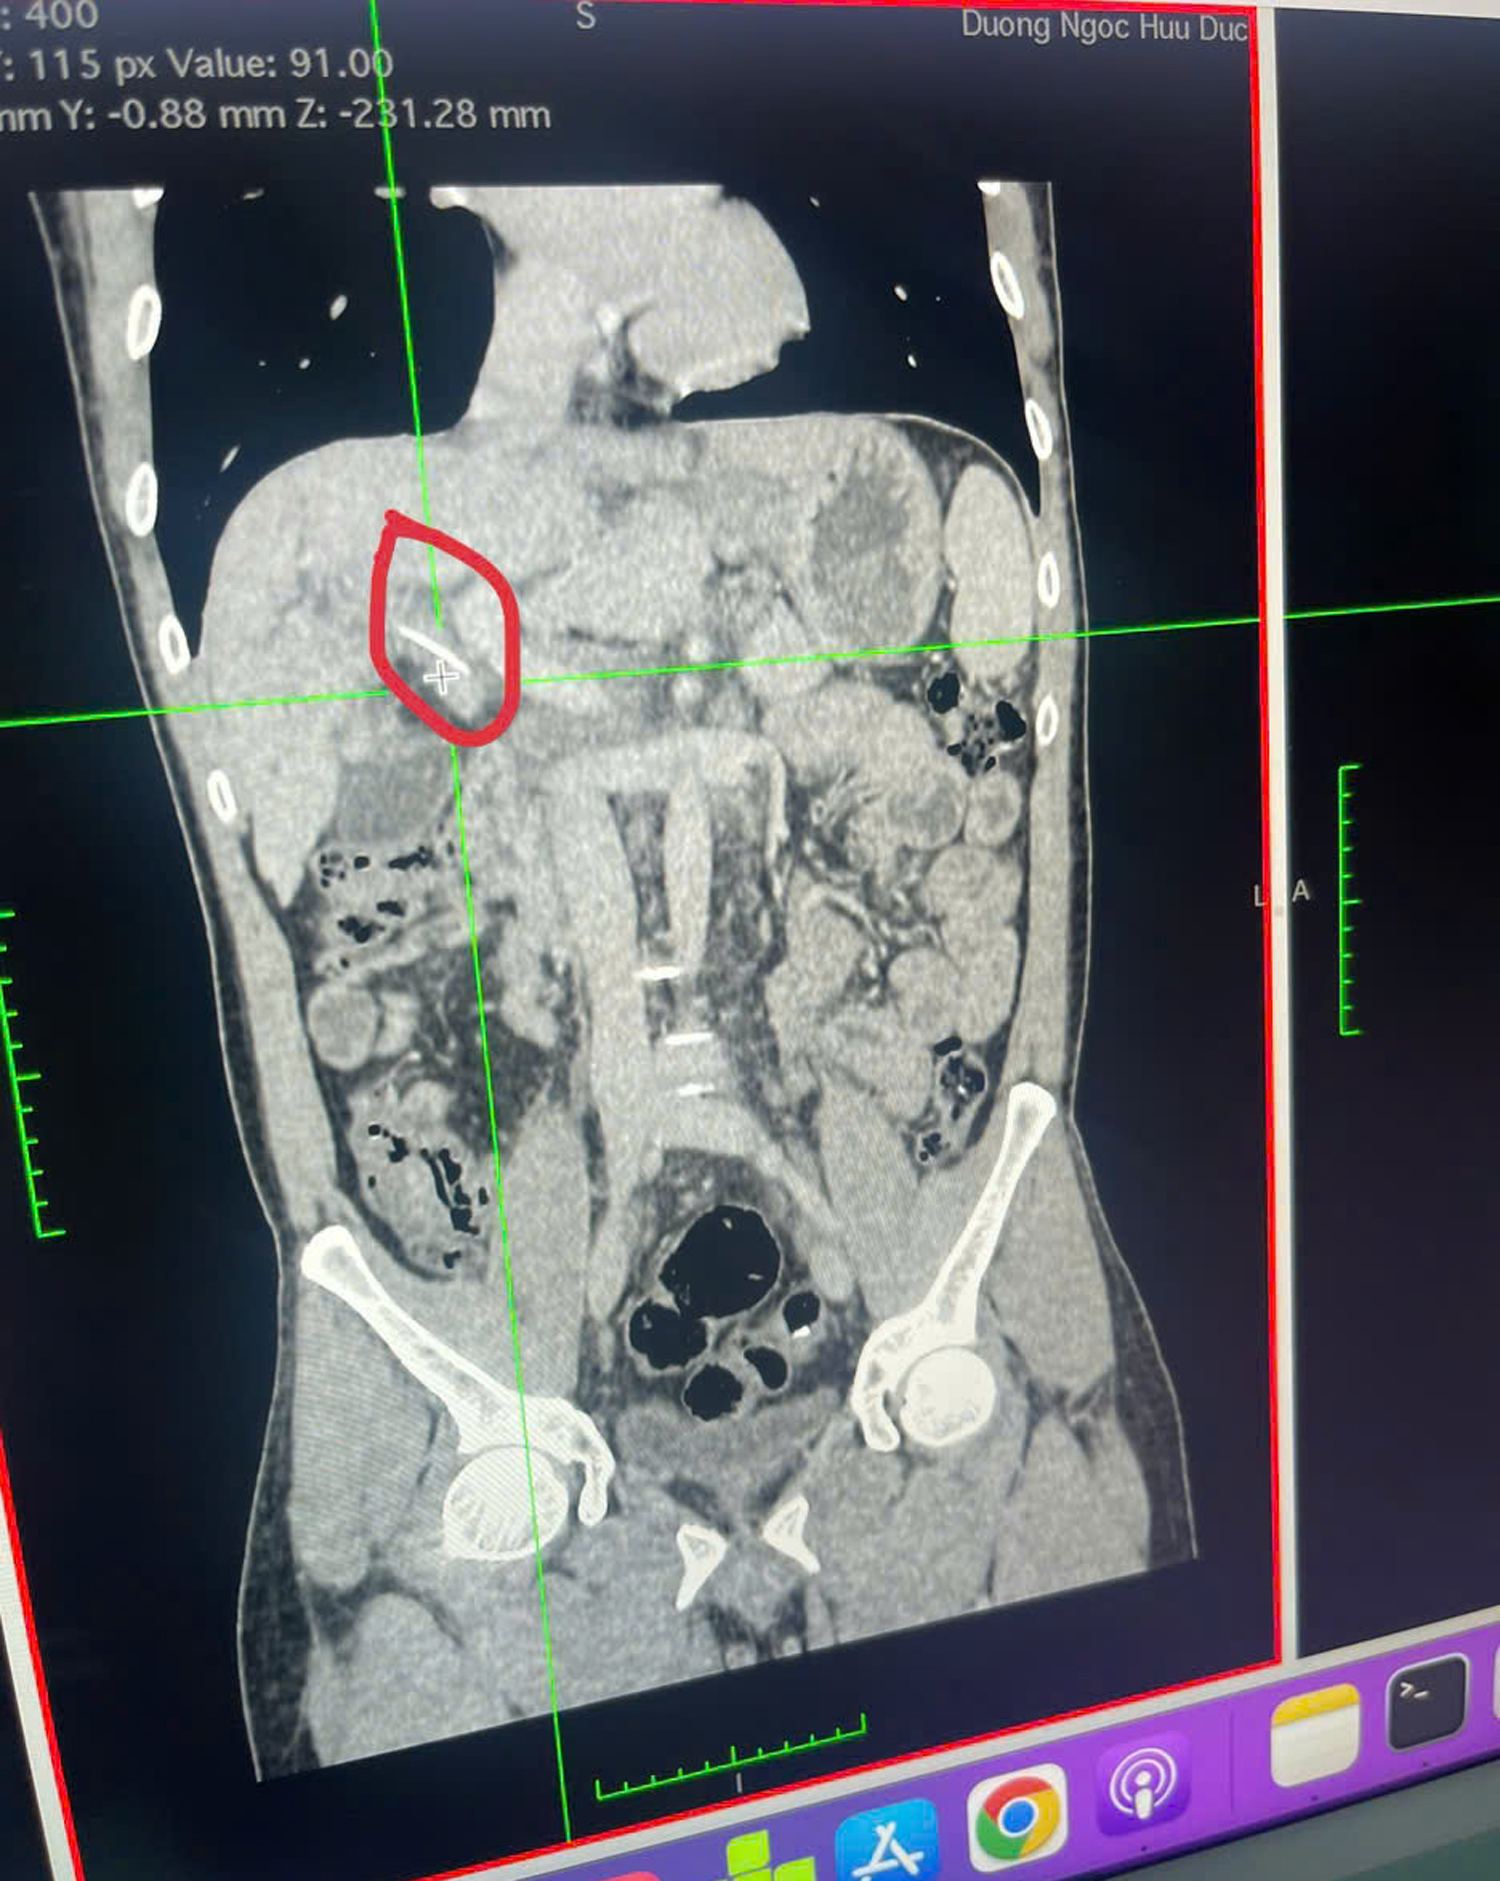

Qua thăm khám và thực hiện các cận lâm sàng, các bác sĩ ghi nhận tình trạng giãn đường mật trong gan, bất thường đường mật vùng rốn gan, chít hẹp đường mật hai nhánh gan đến ống gan chung. Đặc biệt, hình ảnh chụp cắt lớp vi tính cho thấy một dị vật cản quang dài khoảng 2,9 cm vùng rốn gan, nghi ngờ là nguyên nhân gây tắc mật.

Dị vật trên phim chụp cắt lớp vi tính bụng có cản quang và hình ảnh xương cá được lấy ra sau can thiệp.